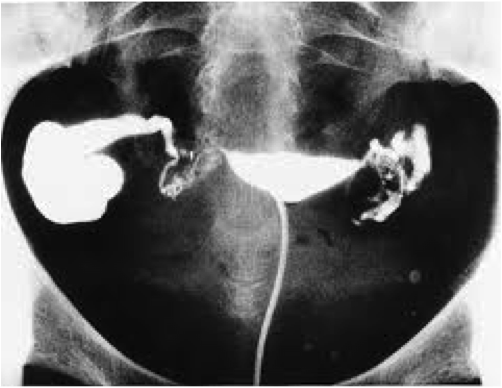

Да. Он у меня. Левая абсолютно не видна, от самого основания. Значи жидкость туда совсем не проникла. Причиной может быть спайка у ее основания, а также причиной может быть мышечный спазме от боли, который полностью ее перекрыл. Я подозреваю, что если бы была видна ее часть, то это уже точно была бы спайка. А тут ее совершенно не видать, как будто ее нет. А врачи делали две попытки пропустить туда жидкость. Когда видели, что левая на экране не видна, они попросили меня повернутьсяна левый бок, расслабиться и снова стали опять вводить жидкость под давлениемконкретно туда. И меня опять так скрутило, что я про себя вспомнила всех святых, рыдала, не могла остановиться. Но левая так и не стала видна. Потом узнала, что до процедуры мне должны были дать обезбаленвание, возможно тогда результат был бы другим.

Насчет непроходимости левой трубы вопрос интересный... Врач, который делал рентген, не взял на себя смелость поставить диагноз о ее непроходимости, поэтому написал, что проходимость не доказана, возможно по причине болевого спазма. Меня там на столе так скрутило, что я волком выла, реально рыдала, хотя я обычно боль терплю как спартанский воин (привыкла к болезненным менструациям). Так вот вполне возможно, что и левая проходима. Как и возможно, что спайки могут быть временным явлением.. в принципе как и их отсутствие тоже..